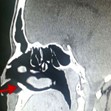

Лекарите са открили зъб в носа на мъж от Саудитска Арабия. Той страдал от постоянно течение на кръв от носа. След хилядите прегледи и изследвания медиците разбрали, че в обонятелния му орган расте не какво и да е, а истински зъб, пише Metro, цитиран от iNews.bg.

22-годишното момче имал проблеми с носа си всеки месец в продължение на 3 години. Накрая лекарите след много прегледи разбрали, че има зъб, който го драска от вътрешната страна на ноздрата и това причинява кървенето.

Лекарите били много изненадани от откритието тъй като момчето имало перфектен набор от зъби в устата си. След проведена операция зъбът, който измъчил момчето е премахнат.